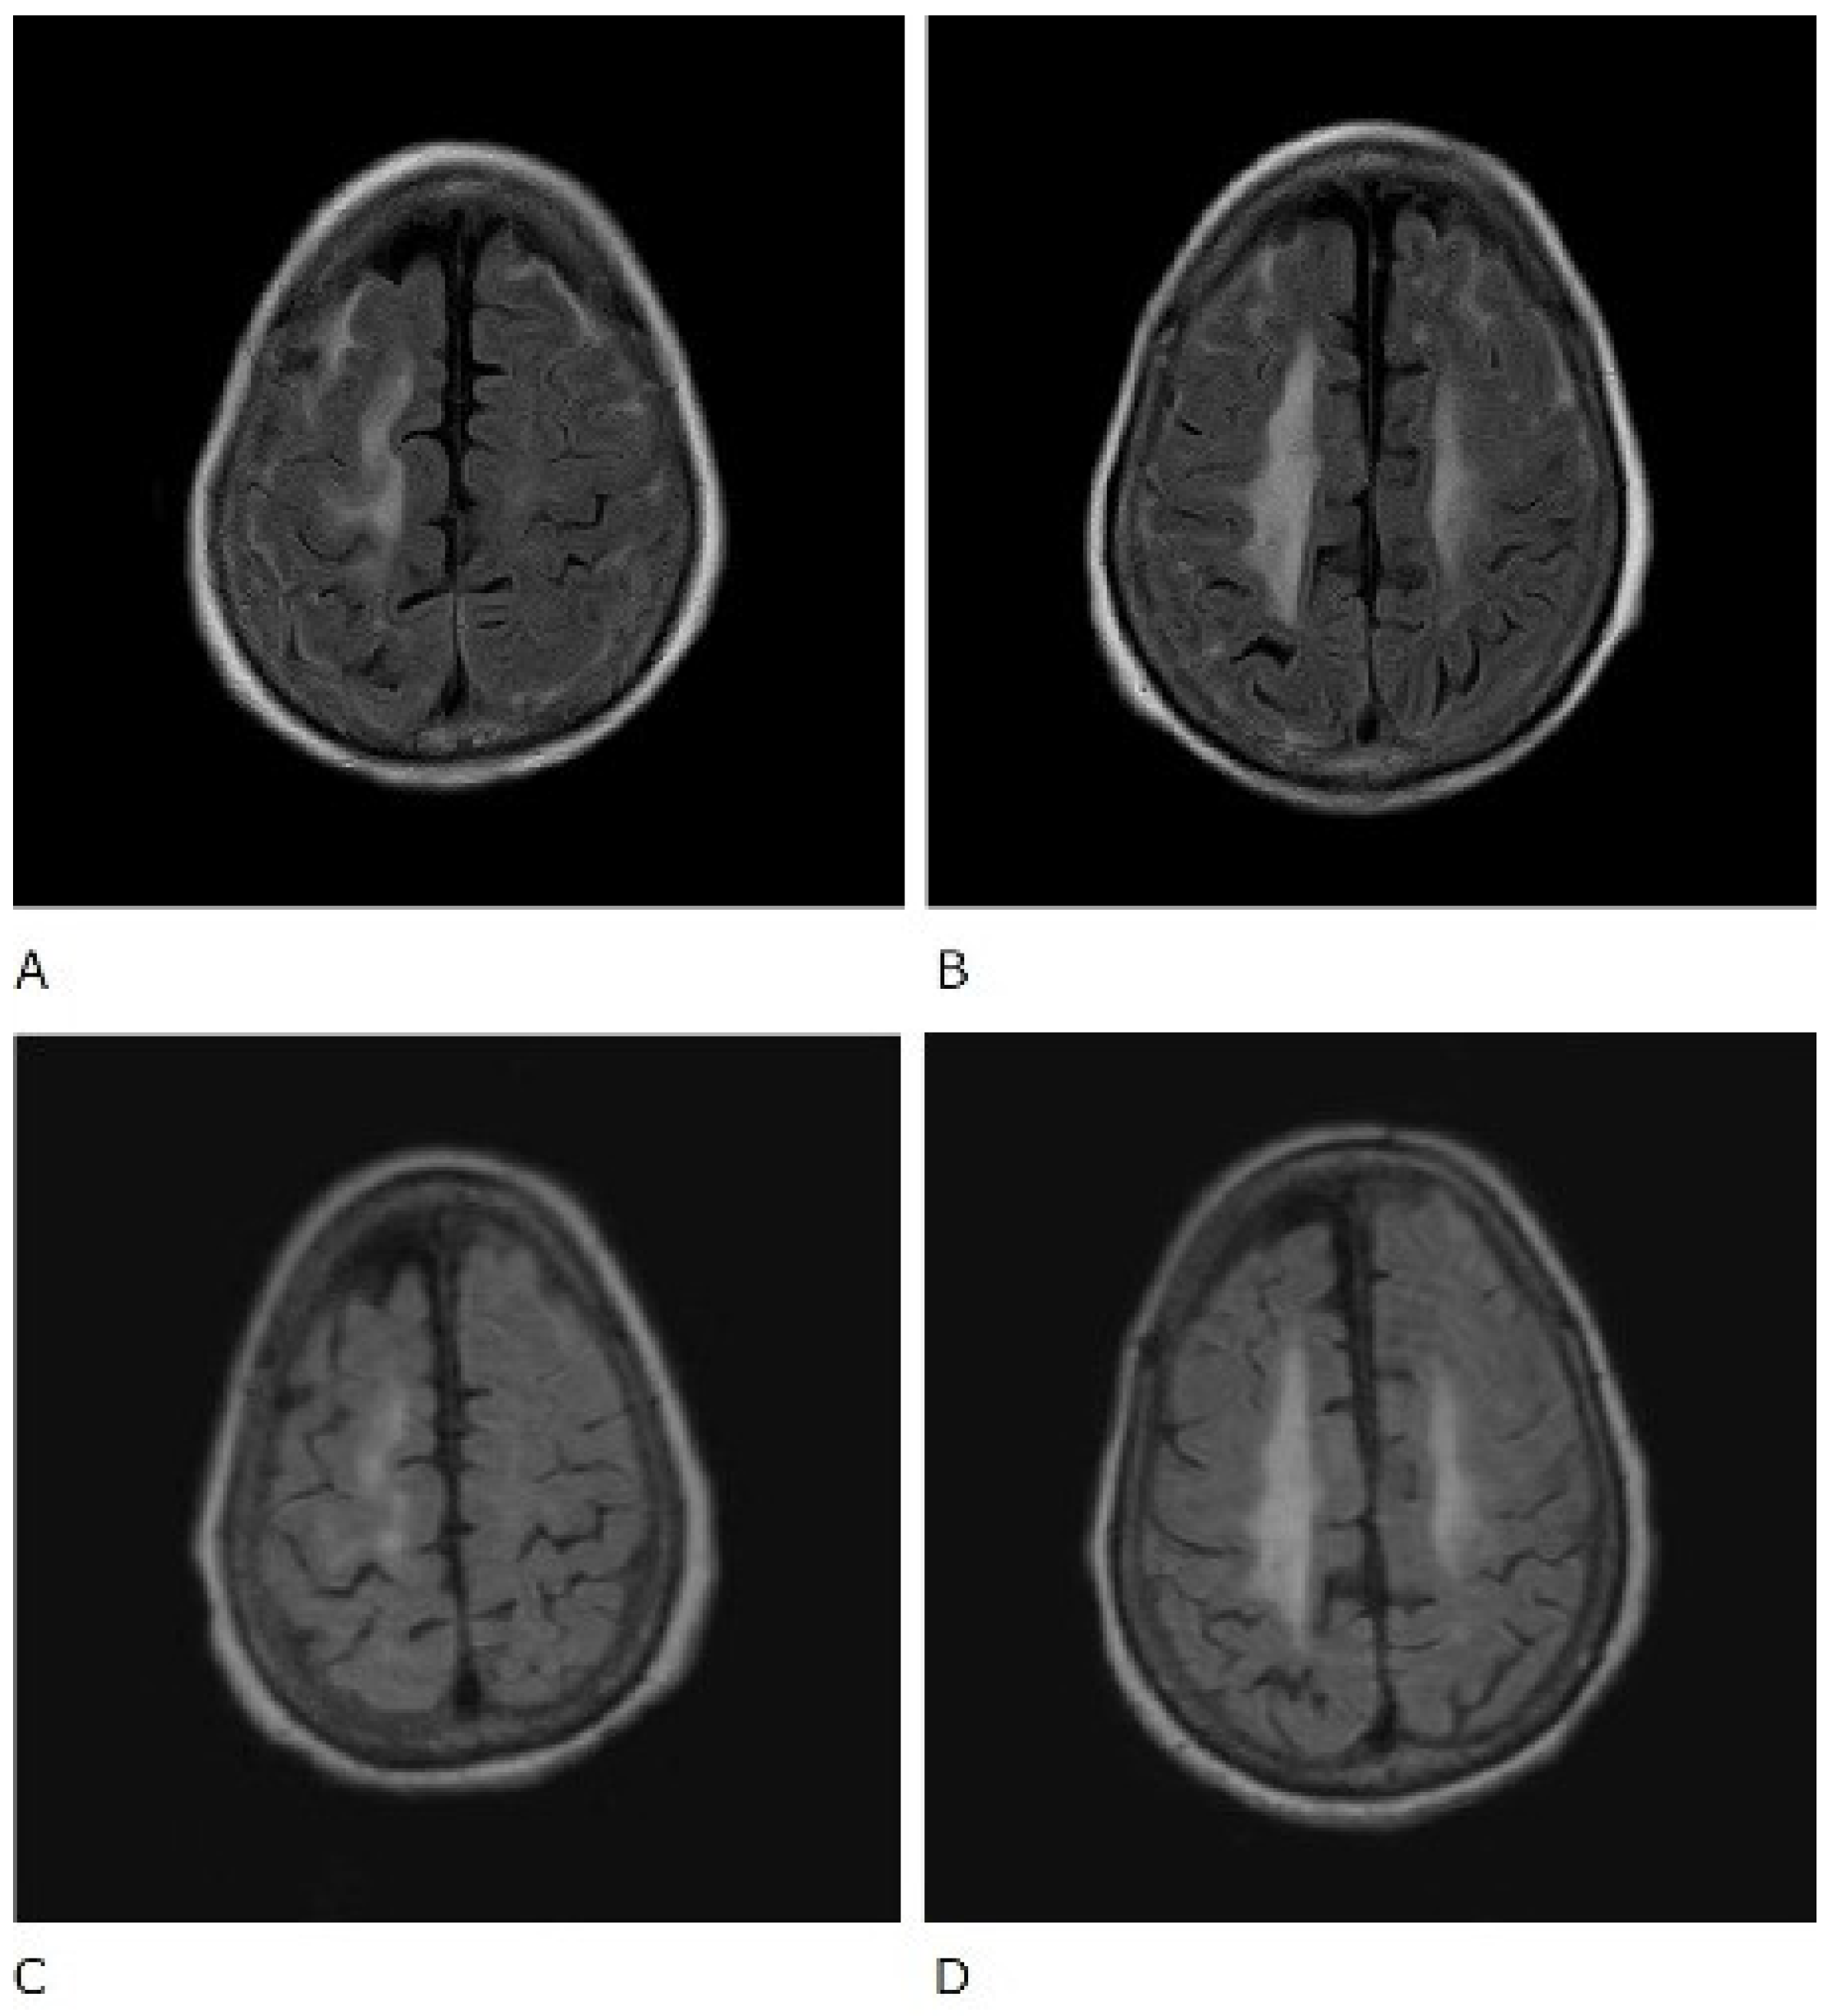

The patient was also tested for infectious diseases but was negative for herpes simplex virus 1, varicella-zoster virus, cytomegalovirus, Epstein–Barr virus, hepatitis B virus, hepatitis C virus, and cryptococcus. Differential diagnosis of non-infectious granulomatous meningitis includes sarcoidosis and tuberculosis. However, there were no other clinical findings, such as bilateral hilar lymphadenopathy, that were indicative of sarcoidosis. Moreover, she had no history of tuberculosis, and a current tuberculosis infection was excluded because no mycobacteria were detected in the CSF; her T-SPOT-TB was negative. Therefore, the patient was diagnosed with rheumatoid meningitis. Prednisolone sodium succinate (40 mg/day; 1 mg/kg/day) was administered by infusion on day 1 to day 9 after admission, and her consciousness level gradually improved. No antibiotics were used. MRI was performed on the 10th day of hospitalisation and showed that the high signal that had been observed in the previous FLAIR sequence had almost disappeared, except in the left frontal region. In contrast, no change was observed in diffuse hyperintensity (T2-WI, FLAIR) of cerebral white matter showing leukoaraiosis (Figure 2 and Figure 3). Since the level of consciousness had improved, her medication was changed to prednisolone 30 mg/day on Day 10 of hospitalisation. On Day 16, her consciousness level recovered to E4V4M6 on the GCS, and she was transferred to another hospital.

Figure 2.

Fluid-attenuated inversion recovery (FLAIR) sequence of brain magnetic resonance imaging. Before treatment (A,B) and after treatment (C,D).